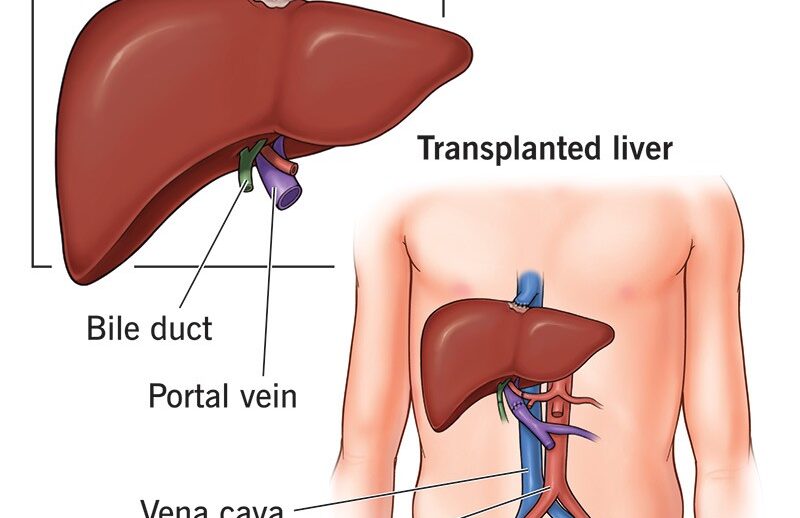

A liver transplant is a major surgical procedure that replaces a diseased, failing liver with a healthy one from a deceased or living donor. It is primarily used to treat acute…

A liver transplant is a major surgical procedure that replaces a diseased, failing liver with a healthy one from a deceased or living donor. It is primarily used to treat acute…